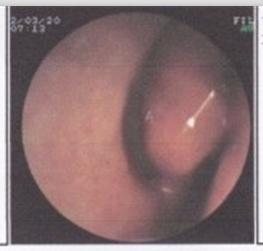

鼻甲肥大有哪些病因

【鼻甲肥大有哪些病因】鼻甲肥大是当今一种很常见的耳鼻喉疾病,鼻甲肥大发病率是很普遍的,由于初期症状并不是很严重,所以很容易被人忽视,错过了最好的治疗时间,导致病情越来越严重,当然也给治疗增加了难度。治疗首先弄清楚鼻甲肥大是怎么回事,只有清楚缘由之后才能根据病因彻底的治疗。